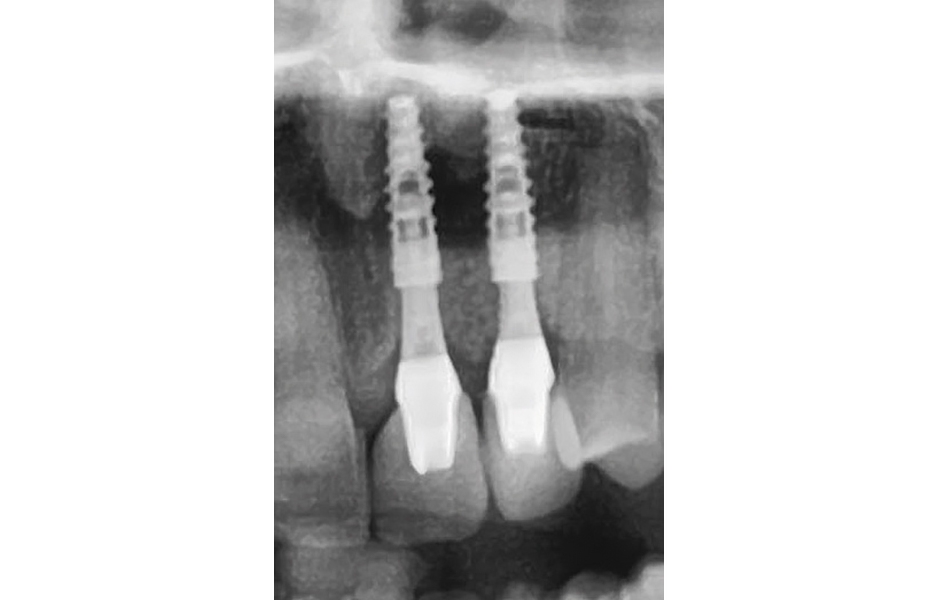

- Obr. 18: Kontrolní rentgenový snímek rok po zavedení implantátů.